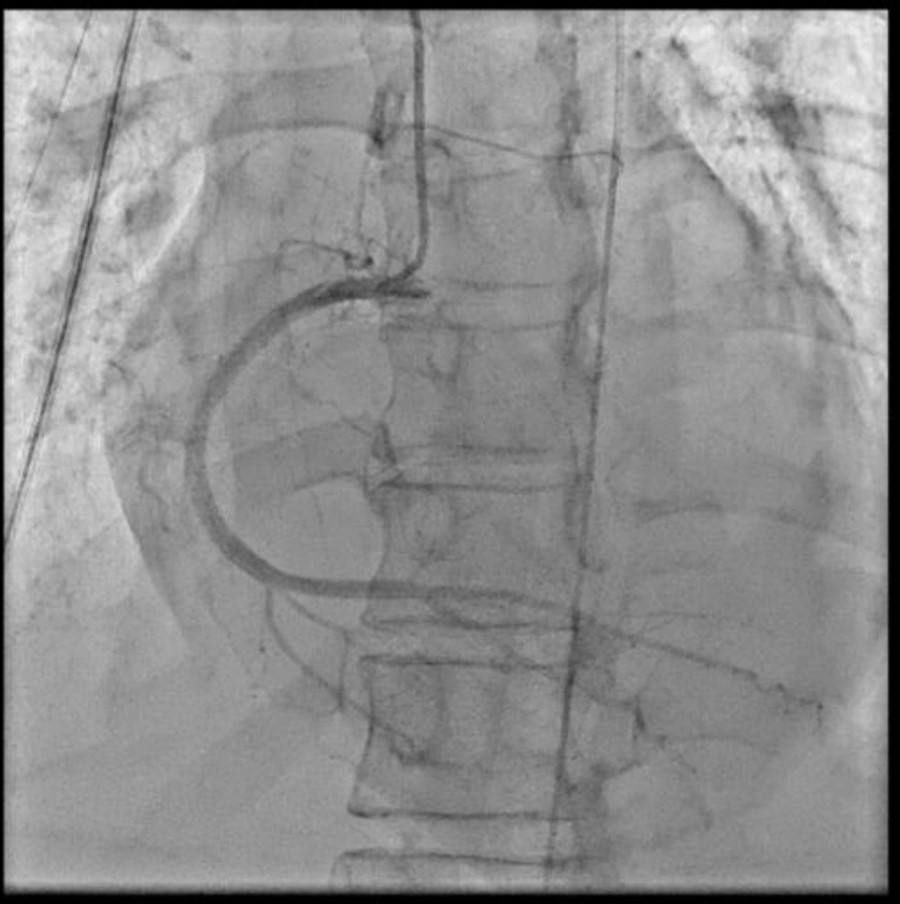

As STEMI could not be ruled out, immediate coronary angiography (CAG) was performed, revealing no significant coronary arteries stenosis. Despite optimal inotropes, cardiogenic shock persisted, prompting intra-aortic balloon pump (IABP) insertion during CAG

Based on the clinical presentation, ECG, and laboratory results, the initial working diagnosis was Anterior STEMI with KILLIP Class IV. CAG was then performed via radial artery using a 6-French introducer sheath, revealing no significant stenosis in the coronary arteries. As the cardiogenic shock still persisted despite optimal inotrope and vasopressor, an IABP was then inserted via femoral artery with the initial setting of 1:2 assist ratio. She was then transferred to the intensive care unit (ICU) where bedside echocardiography revealed a left ventricular ejection fraction (LVEF) of 48% without regional wall motion abnormalities, supporting a non-ischemic etiology. During hospitalization the patient developed acute kidney injury (AKI) with anuria. Further workup for myocarditis showed elevated C-reactive protein (CRP), high procalcitonin levels, and metabolic acidosis. Blood culture was sterile as she had been given antibiotic before. Given rapid clinical deterioration, broad-spectrum antibiotics (meropenem and cefoperazone) were initiated, and hemodialysis was performed. Her condition steadily improved throughout treatment. The IABP was successfully weaned off after four days, and inotropes were gradually tapered off. Serial ECGs also showed gradual resolution of the ST segment elevation and LBBB. After ten days of optimal antibiotics treatment, she continued to improve and was safely discharged from the hospital.